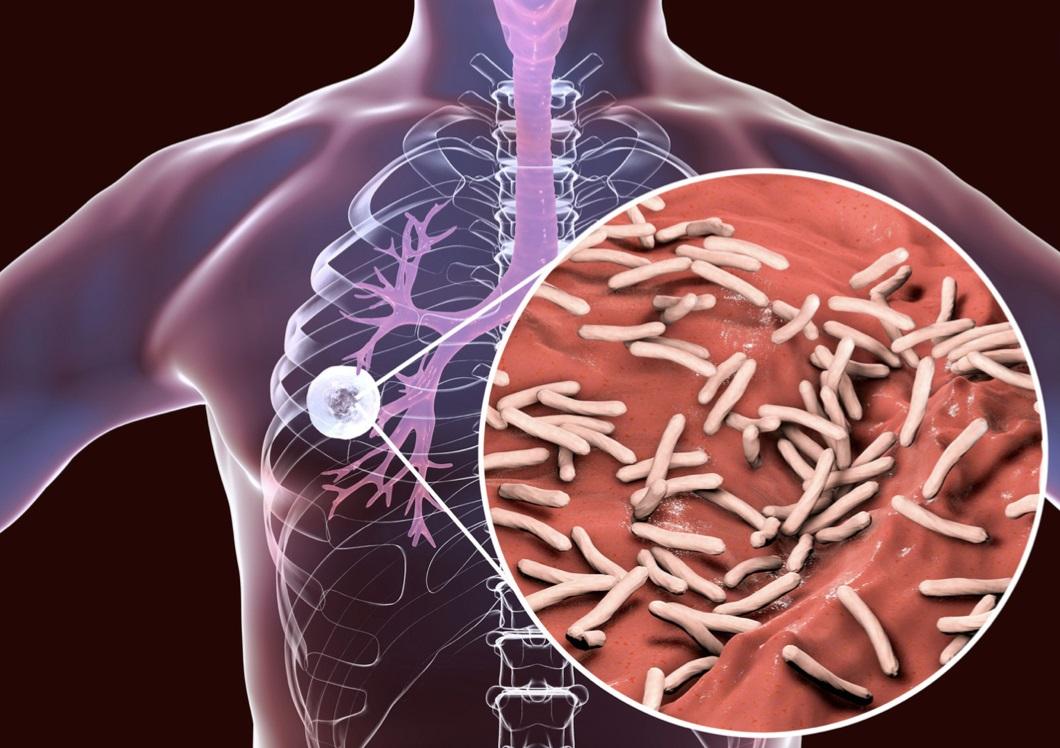

結核病(肺癆)是一種由結核分枝桿菌引起的傳染病,主要影響肺部,但也可以影響其他器官。這是一種嚴重的疾病,若不及時治療,可能導致死亡或其他併發症,如肺部損傷或全身播散性結核病。